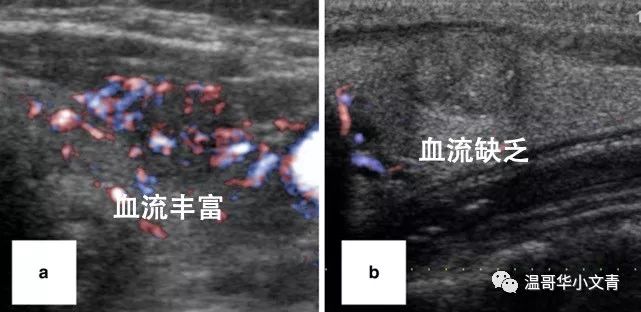

甲癌周边的血流情况不同

肿瘤发展的可能性也会有所不同

图a你可以看到密密麻麻的彩色点点

代表甲癌周边血流丰富

它今后发展的可能性相对大一点

图b甲癌周边几乎没有血流

它今后发展的可能性也就小一点